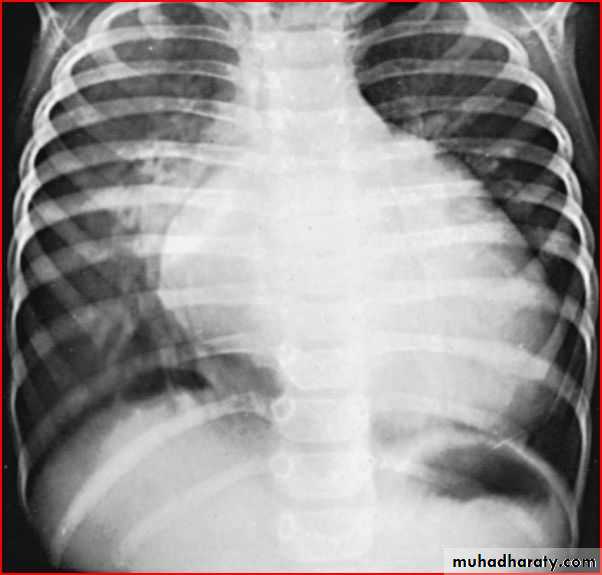

3 month infant presented with cough & dyspnea

Xray shows hyperinflated chest (depresed diaphragm , > 6 ribsMay be bronchiolitis

Hyperinflated chest